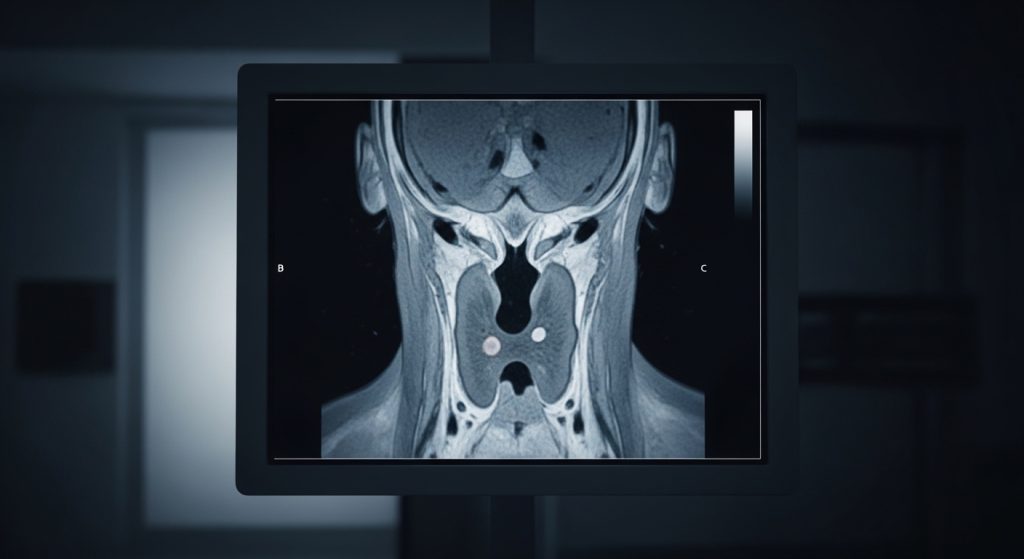

- Imaging (CT, V/Q scan, or other studies): to assess lung structure and evaluate for chronic clots.